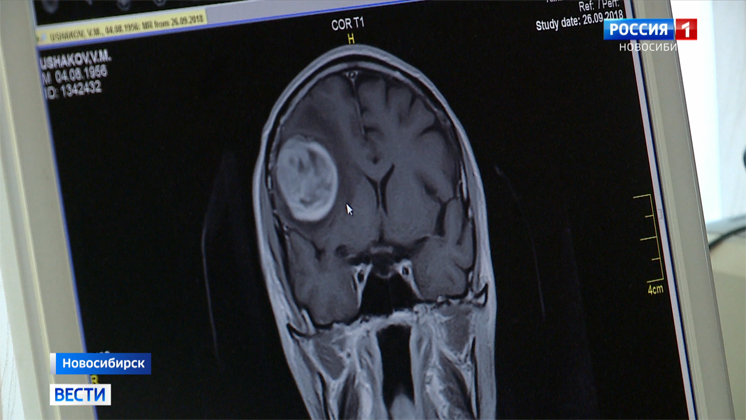

Глиобластома ─ рак головного мозга. Болезнь страшная, агрессивная, в начале своего развития бессимптомная в виде несильных головных болей, но кто обращает на них внимание. Для Владимира Ушакова болезнь наступила внезапно: парализовало левую сторону тела и речь. При 4-й стадии шансы выжить почти нулевые.

─ Профессор Ступак сказал: без вариантов. Если не сделать операцию, то остаются дни, часы жизни, ─ рассказал Владимир Ушаков. Руководитель клиники нейрохирургии №1 ННИИТО Вячеслав Ступак подтвердил, что это очень серьёзное заболевание. По данным МРТ, опухоль у Владимира распространяется глубоко в мозг. Врачи решились на оперативное лечение. Сложная операция прошла успешно. Но это ещё не победа: опухоль часто возвращается. По словам заместителя главного врача по медицинской части, главного специалиста-онколога Вадима Захарова, в таком случае применяется мультикомпонентный подход, комплексное лечение ─ хирургия, химиотерапия и обязательно лучевая терапия.